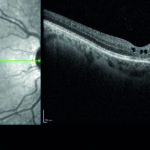

Un’atipica presentazione di retinoschisi X-linked